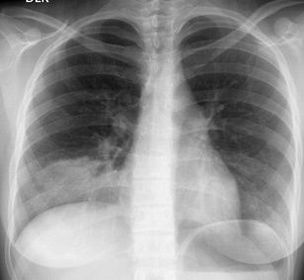

Paciente femenina de 20 años, estudiante de primer año de medicina en época de exámenes de diciembre, la cual refiere cuadro de inicio brusco, caracterizado por escalofríos, fiebre de 40°, debilidad, tos productiva y purulenta, esputo sanguinolento, "dolor en la espalda" el cual es punzante y aumenta al respirar o toser.Comenta que había tenido una "infección de garganta" unos dos días antes de comenzar con el cuadro, con tos productiva y secreción transparente, rinorrea hialina y malestar general.EF: estertores basales, taquicardia, polipnea Rx tórax: infiltrados en lóbulo inferior izquierdo

Caption: : Radiografía de tórax de la paciente